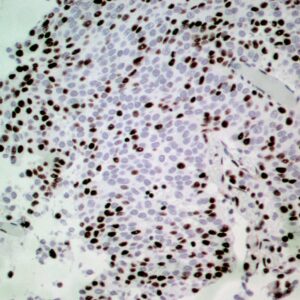

BioGenex has pioneered the development of miRNA research and diagnostics tools with leading-edge products. Currently, we offer over 240 ready-to-use (RTU) Super Sensitive™ Nucleic Acid (SSNA) miRNA ISH probes for accurate and early tumor diagnosis. These probes are sensitive enough to detect low-abundant miRNA(s) that are often required to identify biomarkers. They have a high melting temperature enabling stringent washes to remove non-specific binding. BioGenex miRNA probes are dual-end labeled with an anti-fluorophore to amplify the signal and yield clean and intense staining.